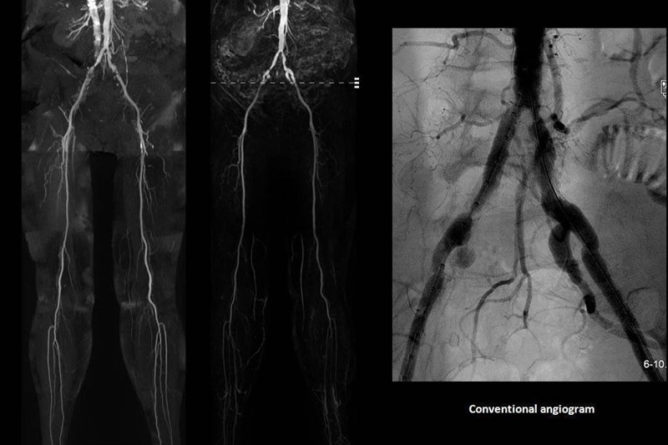

ANGIOGRAM

Angioplasty

You or your relative or your friend might have had symptoms such chest pain, shortness of breath or…